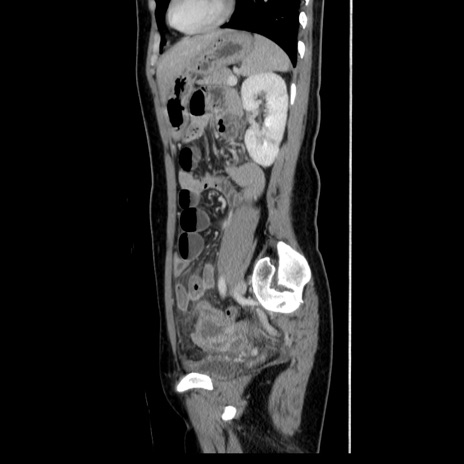

症例39(矢状断像)

【症例】40歳代女性

【主訴】上下腹部痛

【現病歴】2日目から下腹部痛あり。夜間は痛みで眠れなかった。昨日より上腹部痛と下痢が出現。臥位で痛みは軽快したため、休んでいた。本日になって臥位でも立位でも痛みが強くなってきたため救急要請。

【既往歴】子宮内膜症

【身体所見】部:平坦・軟、左上下腹部に圧痛あり、反跳痛あり。

【データ】WBC 21800、CRP 26.78

CT